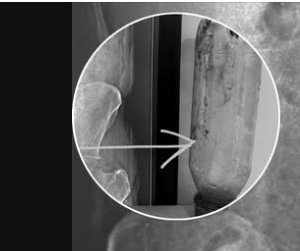

एक जन आगरा और एक जन अहमदाबाद दोनों कट्टर कांग्रेसी रहे,दिन में राहुल गांधी की रैली में मोई जी के खिलाफ में गए थे और रात में पौवा पी कर घर में बैठे न्यूज देख रहे थे अचानक से मोई जी को TV में देख लिए अचानक उनके गेंद में कीड़ा बिलबिलाने लगा खुजली शांत करने के लिए दोनों अपने घर में रखे बोतल गेंद में रख कर खुजली शांत करने लगे😂😂खुजली तो शांत हो गई होश में आते ही गांव का गुड़गांव बन गया तेज दर्द में दोनों डॉक्टर के पास भागे डॉक्टर ने पूछा मोदी विरोधी हो? दोनों ने बोला हां, डॉक्टर ने बोला तभी इतना स्पेस बन गया खैर डॉक्टर ने हाथ डालकर बोतल निकाल दिया 😂😂